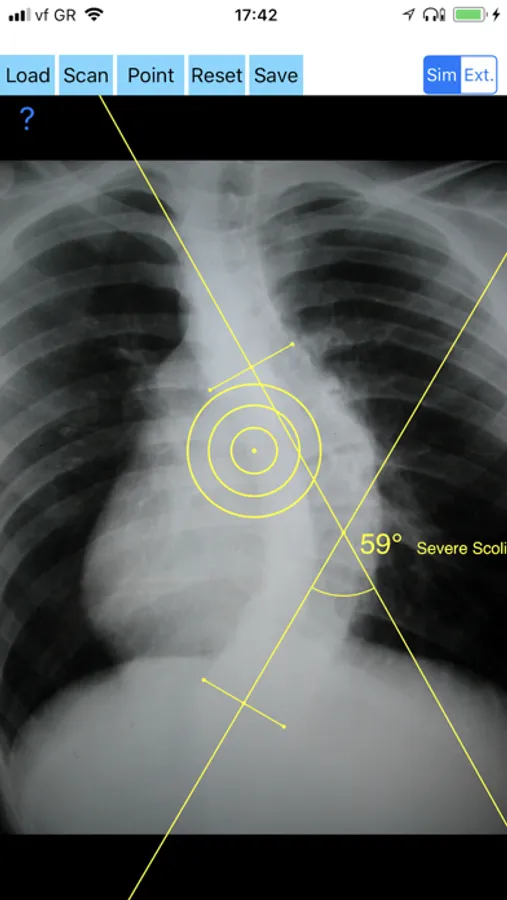

-Offers a very convenient way to determine the most accurate possibly way at once. By marking four points at the same X-ray, at each spine the App calculates the Cobb angle. In cases where values are out of normal ranges, the scoliosis is categorized according to measured angle as mild, moderate, severe. To simplify the process and to minimize inter-observer errors usually by not selecting the actual end vertebra, the app offers also in ext mode the ability to draw the vertical reference line through the patient’s sacrum and to identify more easily the end vertebrae s (ext method).

CobbAngleApp Screenshots